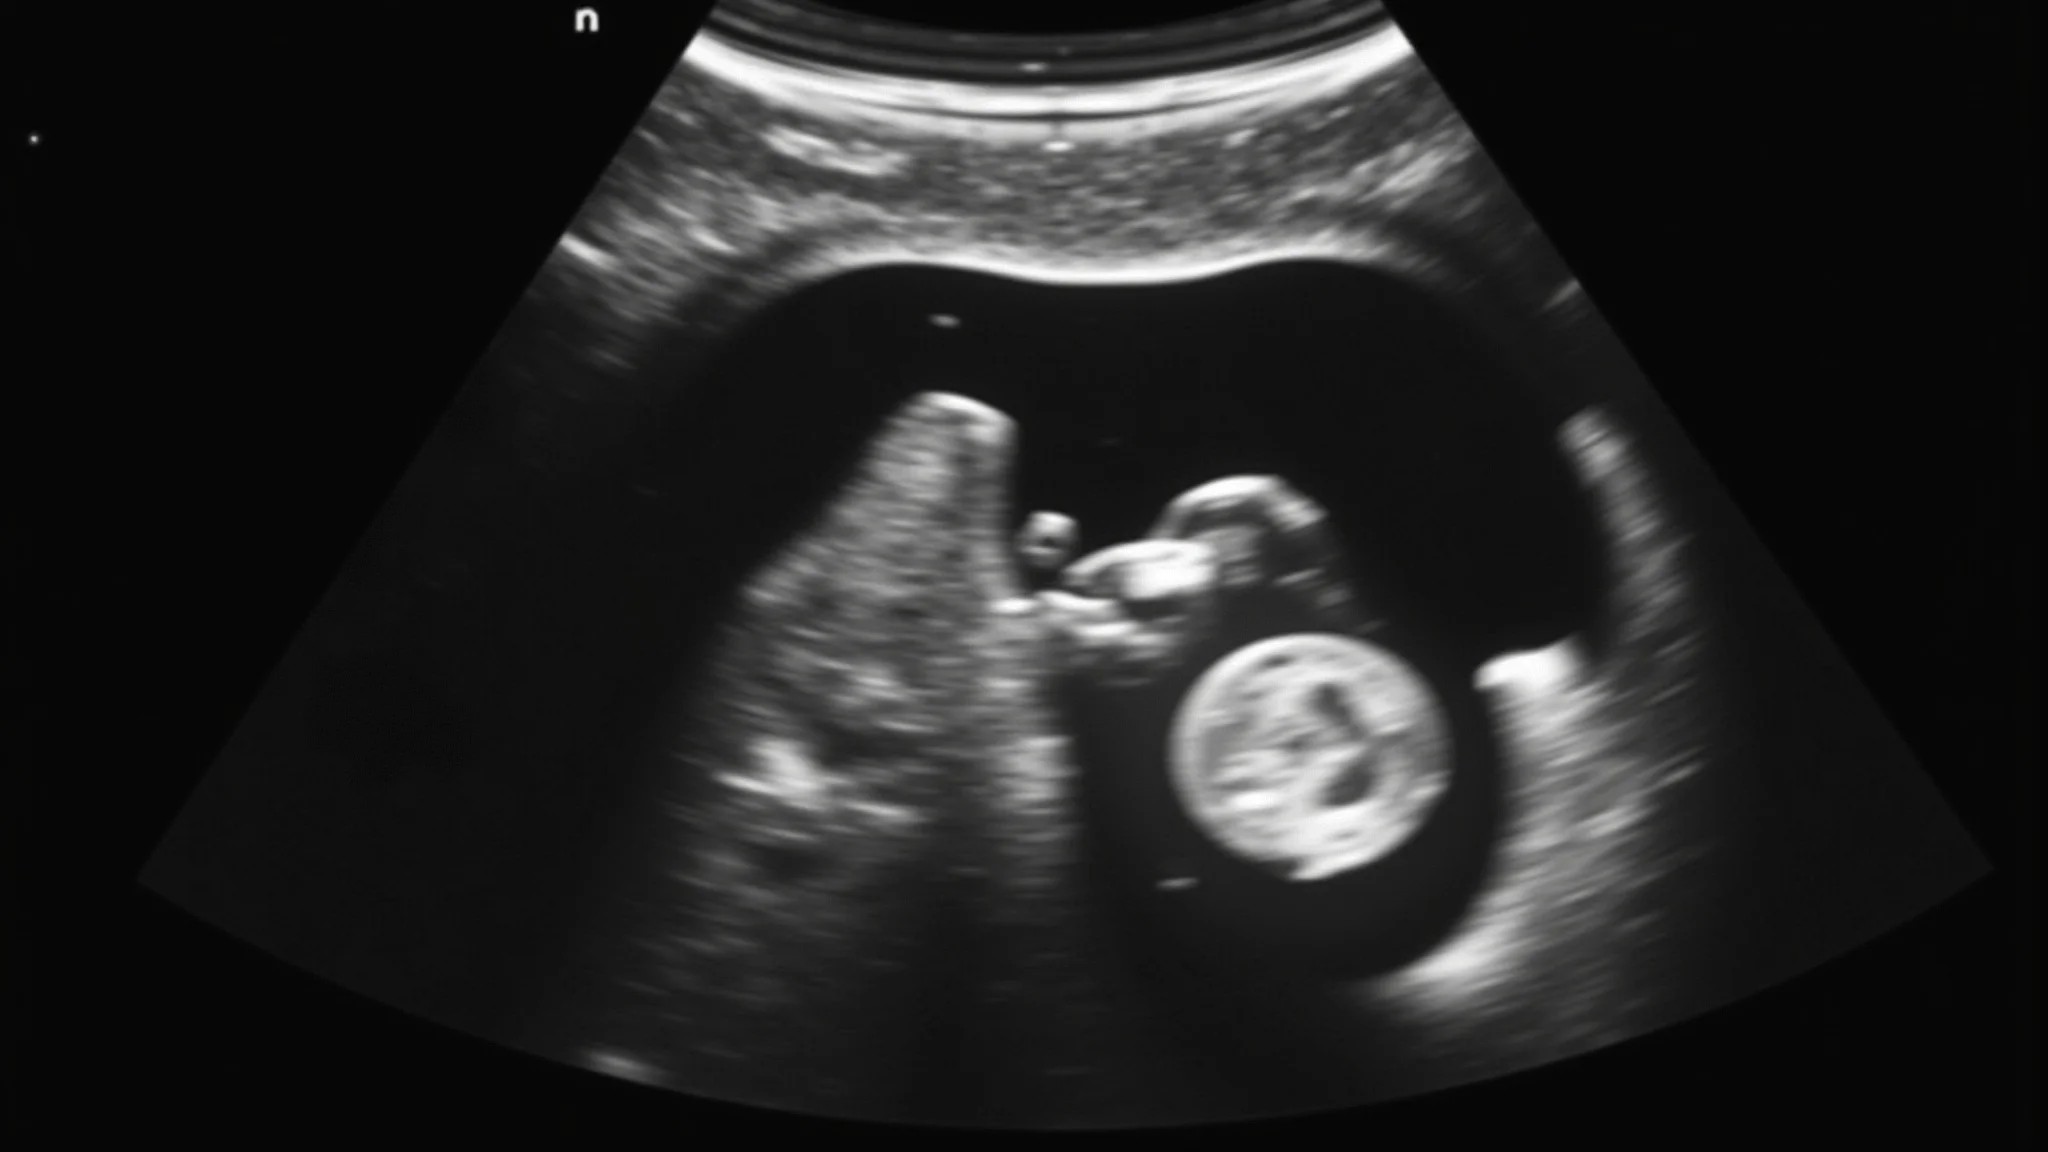

Semana 20: O Sexo do Bebê e os Primeiros Chutes

A tão esperada ultrassonografia morfológica! É nessa fase que geralmente descobrimos o sexo do bebê. E, prepare-se, os chutes ficam cada vez mais fortes e frequentes. Uma delícia!